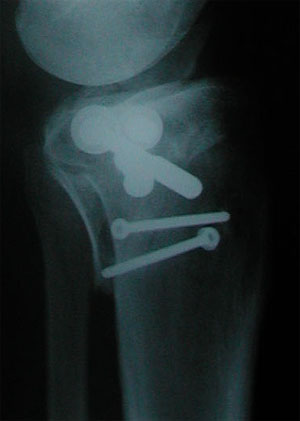

Röntgenbild (Seitenansicht) vom 7. Juli 2001. Das am linken Rand des Schienbeinkopfs sichtbare, vorstehende Teil sollte im Lauf der Zeit wieder besser einwachsen.

... das Röntgenbild vom 7. Juli 2001: Zwischen dem abstehenden, mit der untersten Schraube fixierten Teil und dem Schienbein klafft noch eine deutliche Lücke.